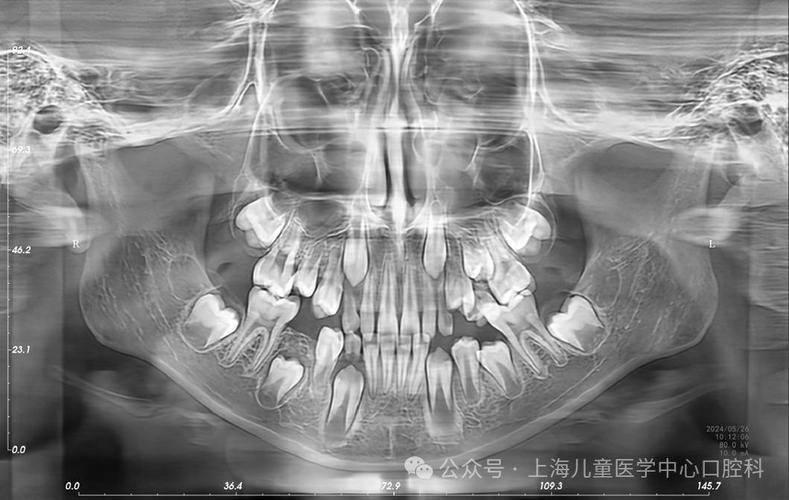

- 收益远大于风险: 片子能帮助医生发现肉眼看不见的早期蛀牙、牙槽骨吸收、埋伏牙、囊肿等问题,为制定精准、有效的治疗计划提供关键依据,其带来的健康收益远远大于微乎其微的辐射风险。